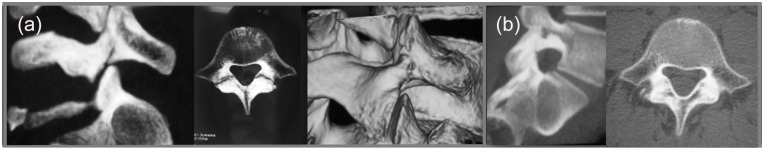

Abstract Image